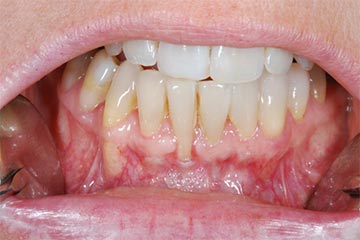

Lembo libero per correggere una recessione gengivale